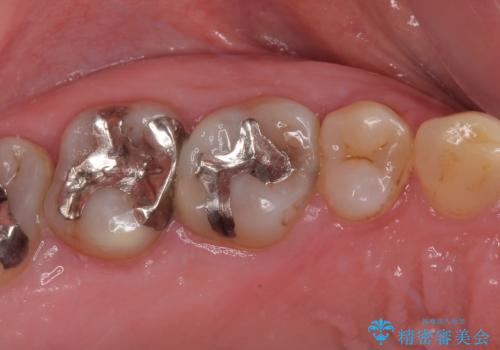

また、裏打ちに主に銀を用いた金属材料を使用するため、金属自体が黒くなったり、イオンとなり溶け出したりして、歯肉ラインが黒くなってしまうことがあります。

一部は根管治療を行い、土台の金属も歯の色に近いものへと変更した上で、オールセラミッククラウンにて補綴することとしました。

虫歯の進行などはさほど認められなかったので、根管治療実施後に速やかにオールセラミッククラウンにて補綴しました。